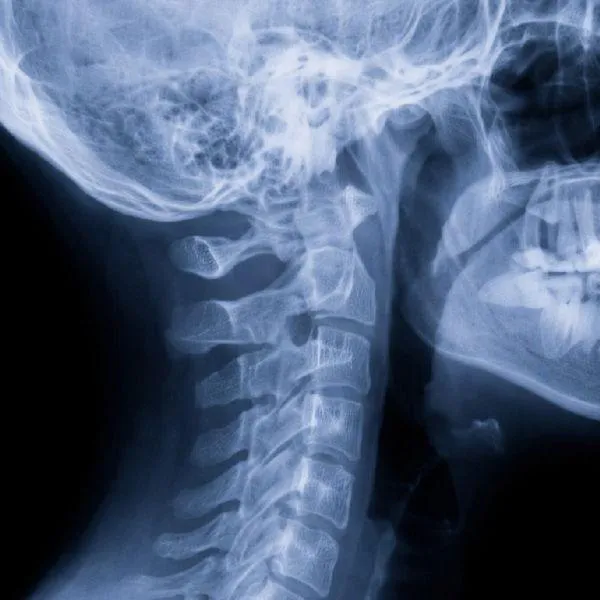

Digital X-ray technology has transformed how chiropractors evaluate spinal alignment, joint health, and overall biomechanics. Compared to traditional film X-rays, digital imaging provides clearer imag... ...more